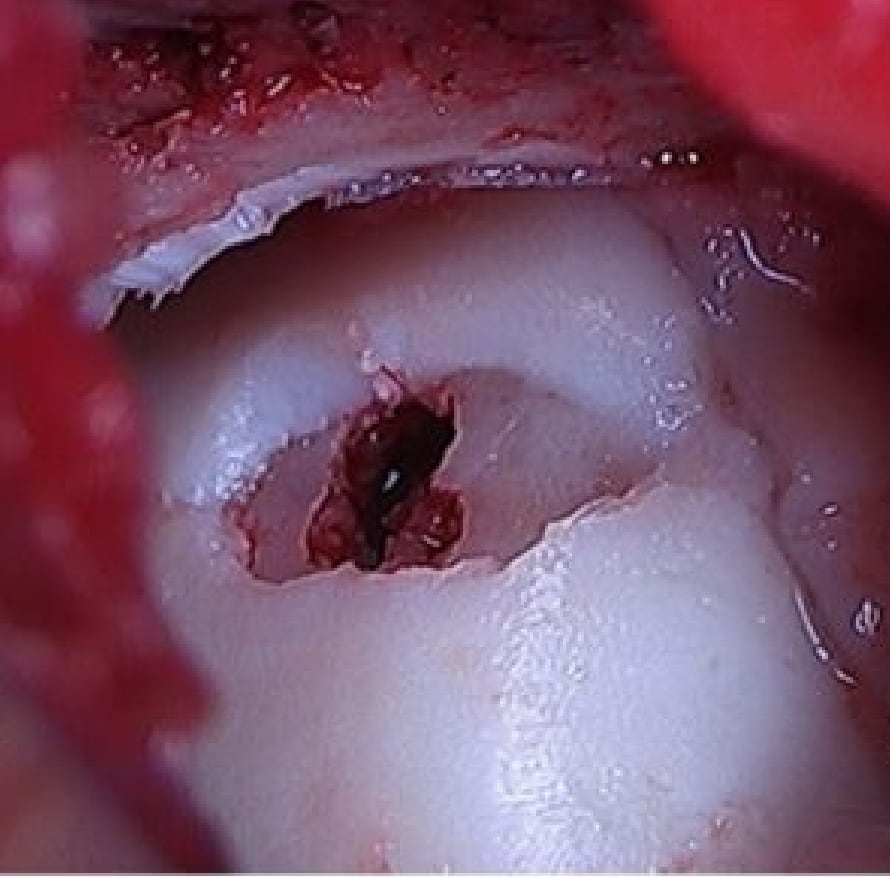

2020-12-09 スポーツ整形 ページ内リンク 距骨骨軟骨損傷(離断性骨軟骨炎)【スポーツ整形外科】 距骨骨軟骨損傷(離断性骨軟骨炎)【スポーツ整形外科】 軟骨とその下の骨が剥がれてきて痛みが出る。⇒骨穿孔/骨軟骨片固定/骨軟骨柱移植 患部の状態により最適な治療方法を選択します。 骨軟骨柱移植前 骨軟骨柱移植後 骨軟骨柱移植術後CT 関連ページ スポーツ整形 一覧へ戻る